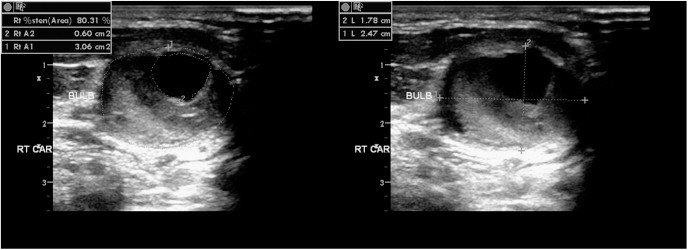

죽상경화 플라크 성상 평가

플라크는 저에코(연성), 등·고에코(섬유·석회화), 표면 불규칙·궤양 등으로 묘사됩니다. 영상에서 연성·불안정 소견은 색전 위험과 연관될 수 있어 주의 깊은 추적과 치료 최적화가 권장됩니다.

- 진단 문구 예시: ‘우측 ICA 근위부 중등도 협착 의심’, ‘양측 CCA 분지부 석회화 플라크’, ‘좌측 IMT 증가’.